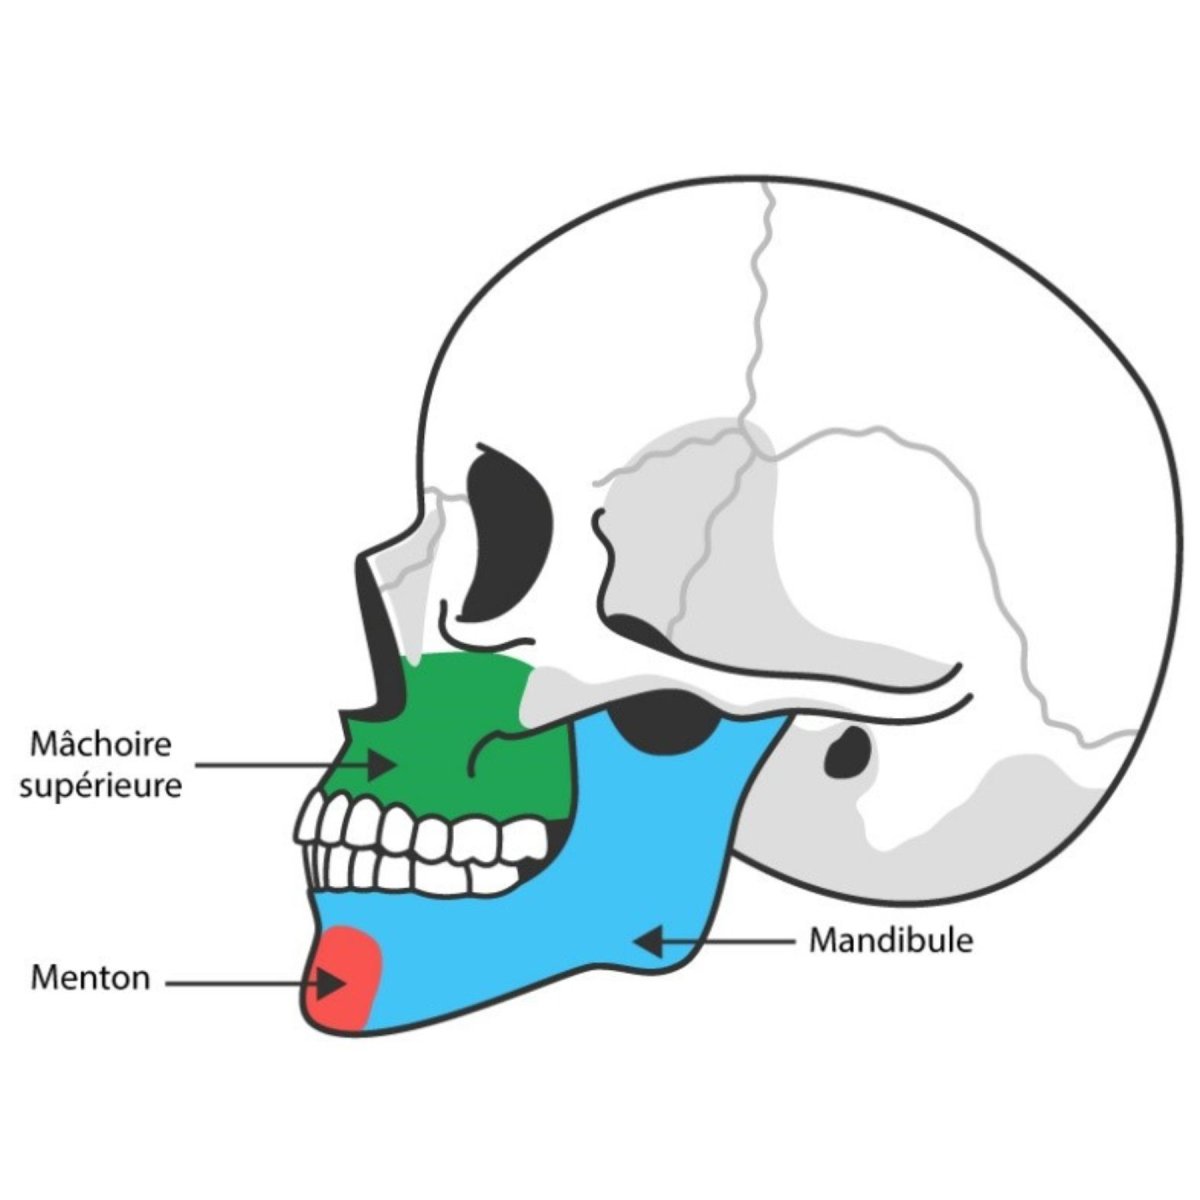

La physiothérapie maxillo-faciale correspond à la physiothérapie qui s’occupe des troubles et symptômes liés à l’articulation temporo-mandibulaire, la mâchoire, la bouche, le crâne, la face et le cou.

Chirurgie orthographique - Fiche d'éducation thérapeutique

Retrouver le feuille d'éducation thérapeutique concernant la chirurgie orthographique sur le blog de CapRol.

- Quelques définitions

- Objectif d'une chirurgie orthographique